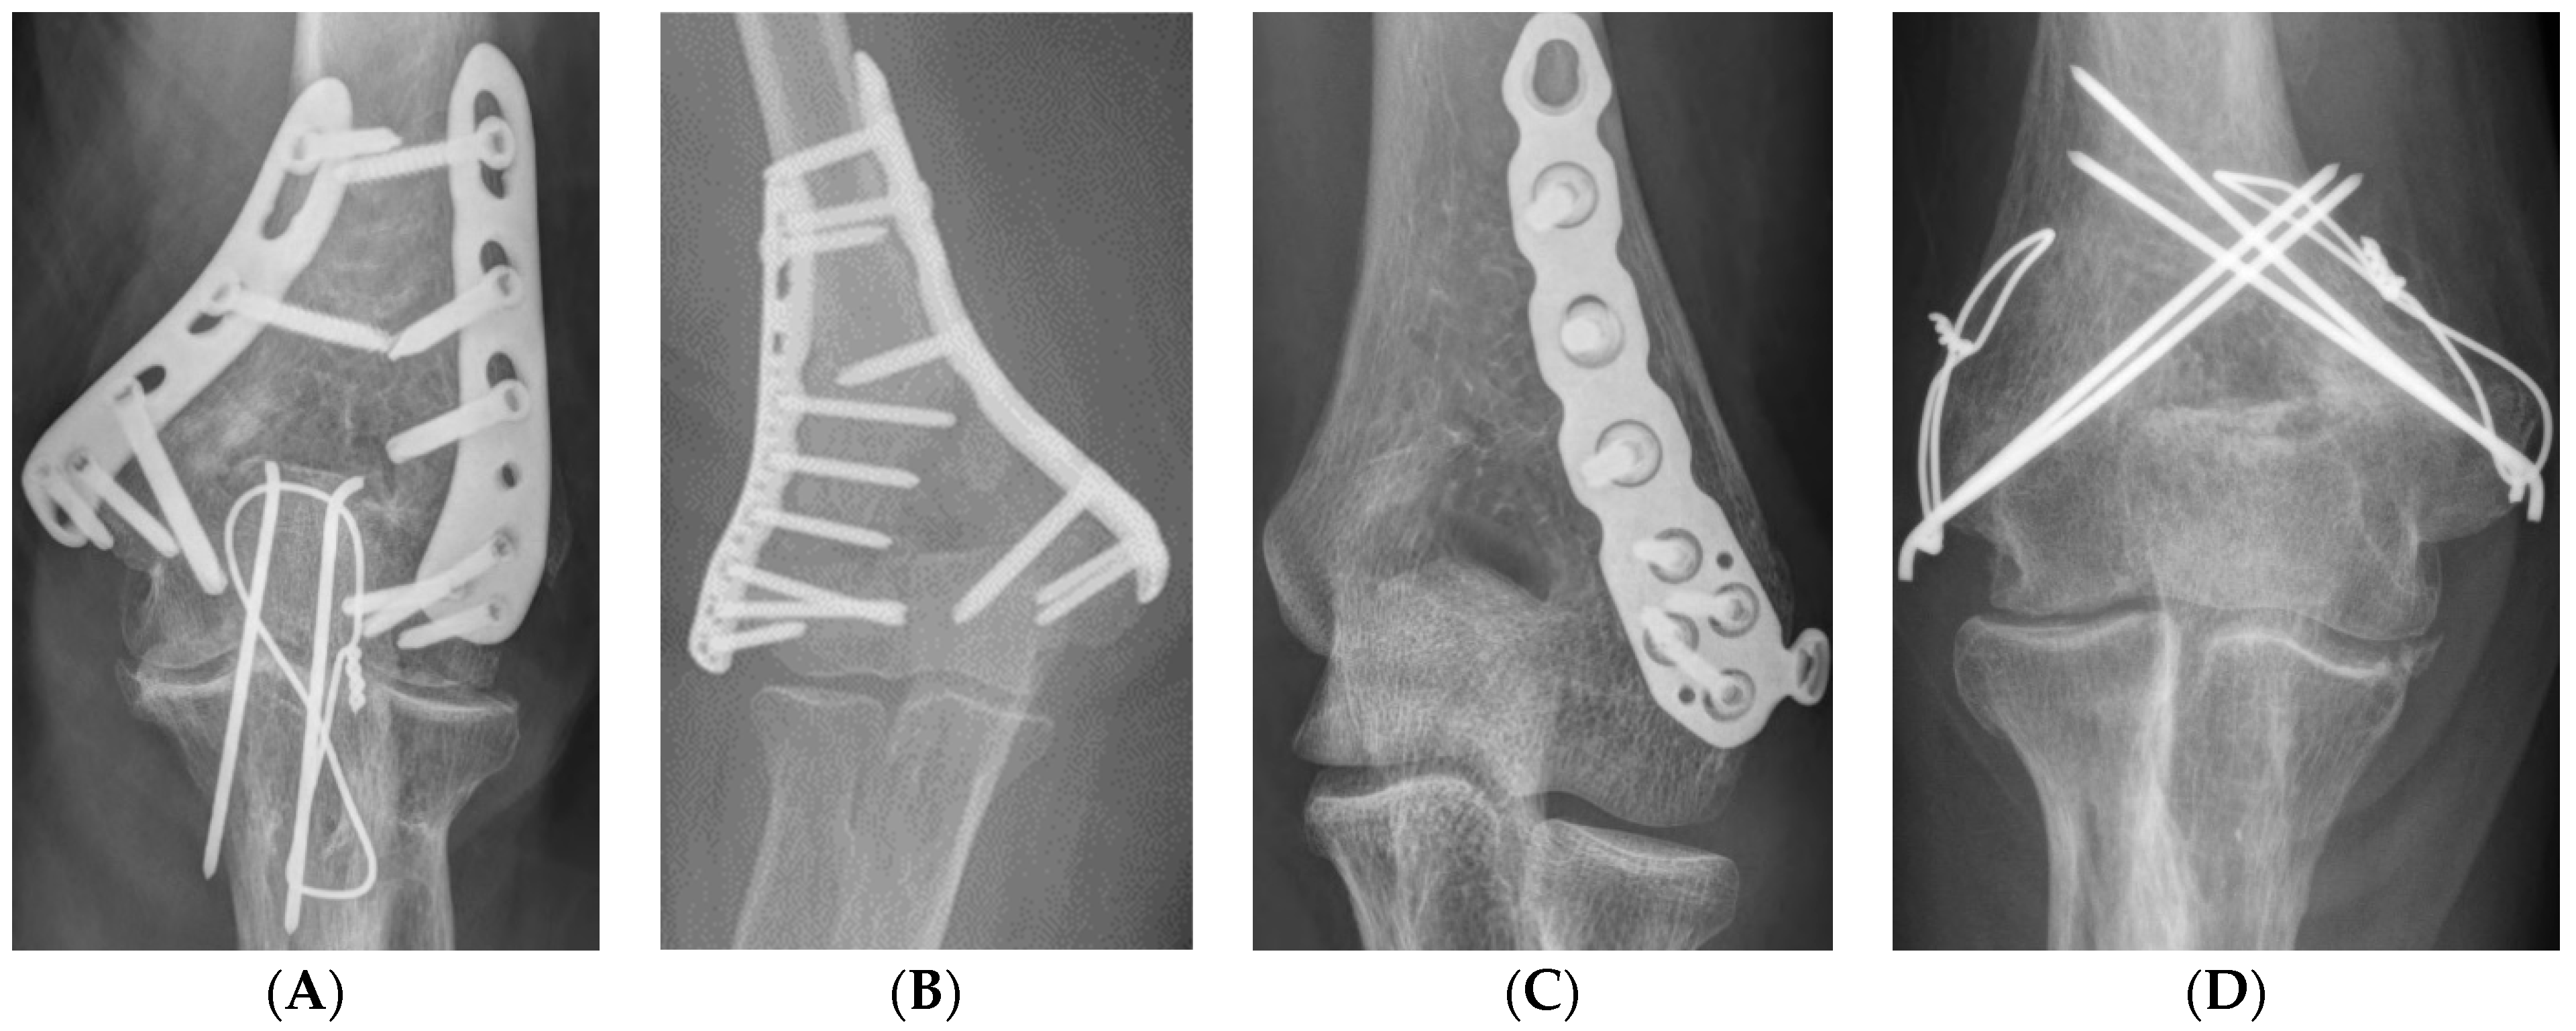

In the case of the combined mediolateral approach, as in Wei et al. [18], the medial incision was performed first and the ulnar nerve was identified but not released. A reduction clamp was used to hold the medial side of the proximal and distal fragments, and one or two Kirschner wires were used for temporary fixation. Subsequently, the lateral side of the fracture fragment was approached through a lateral incision and temporary fixation was performed in the same way, and then a 3.5 LCP distal humerus plate (DuPey Synthes, West Chester, PA, USA) was applied either orthogonally or parallelly (Figure 2A–D).

Figure 2.

Dual incision (A) medial approach, identification of ulnar nerve (arrow), temporary fixation using two Kirschner wires, (B) lateral incision, temporary fixation using one Kirschner wire, (C) intraoperative C-arm radiograph, (D) orthogonal plate fixation.